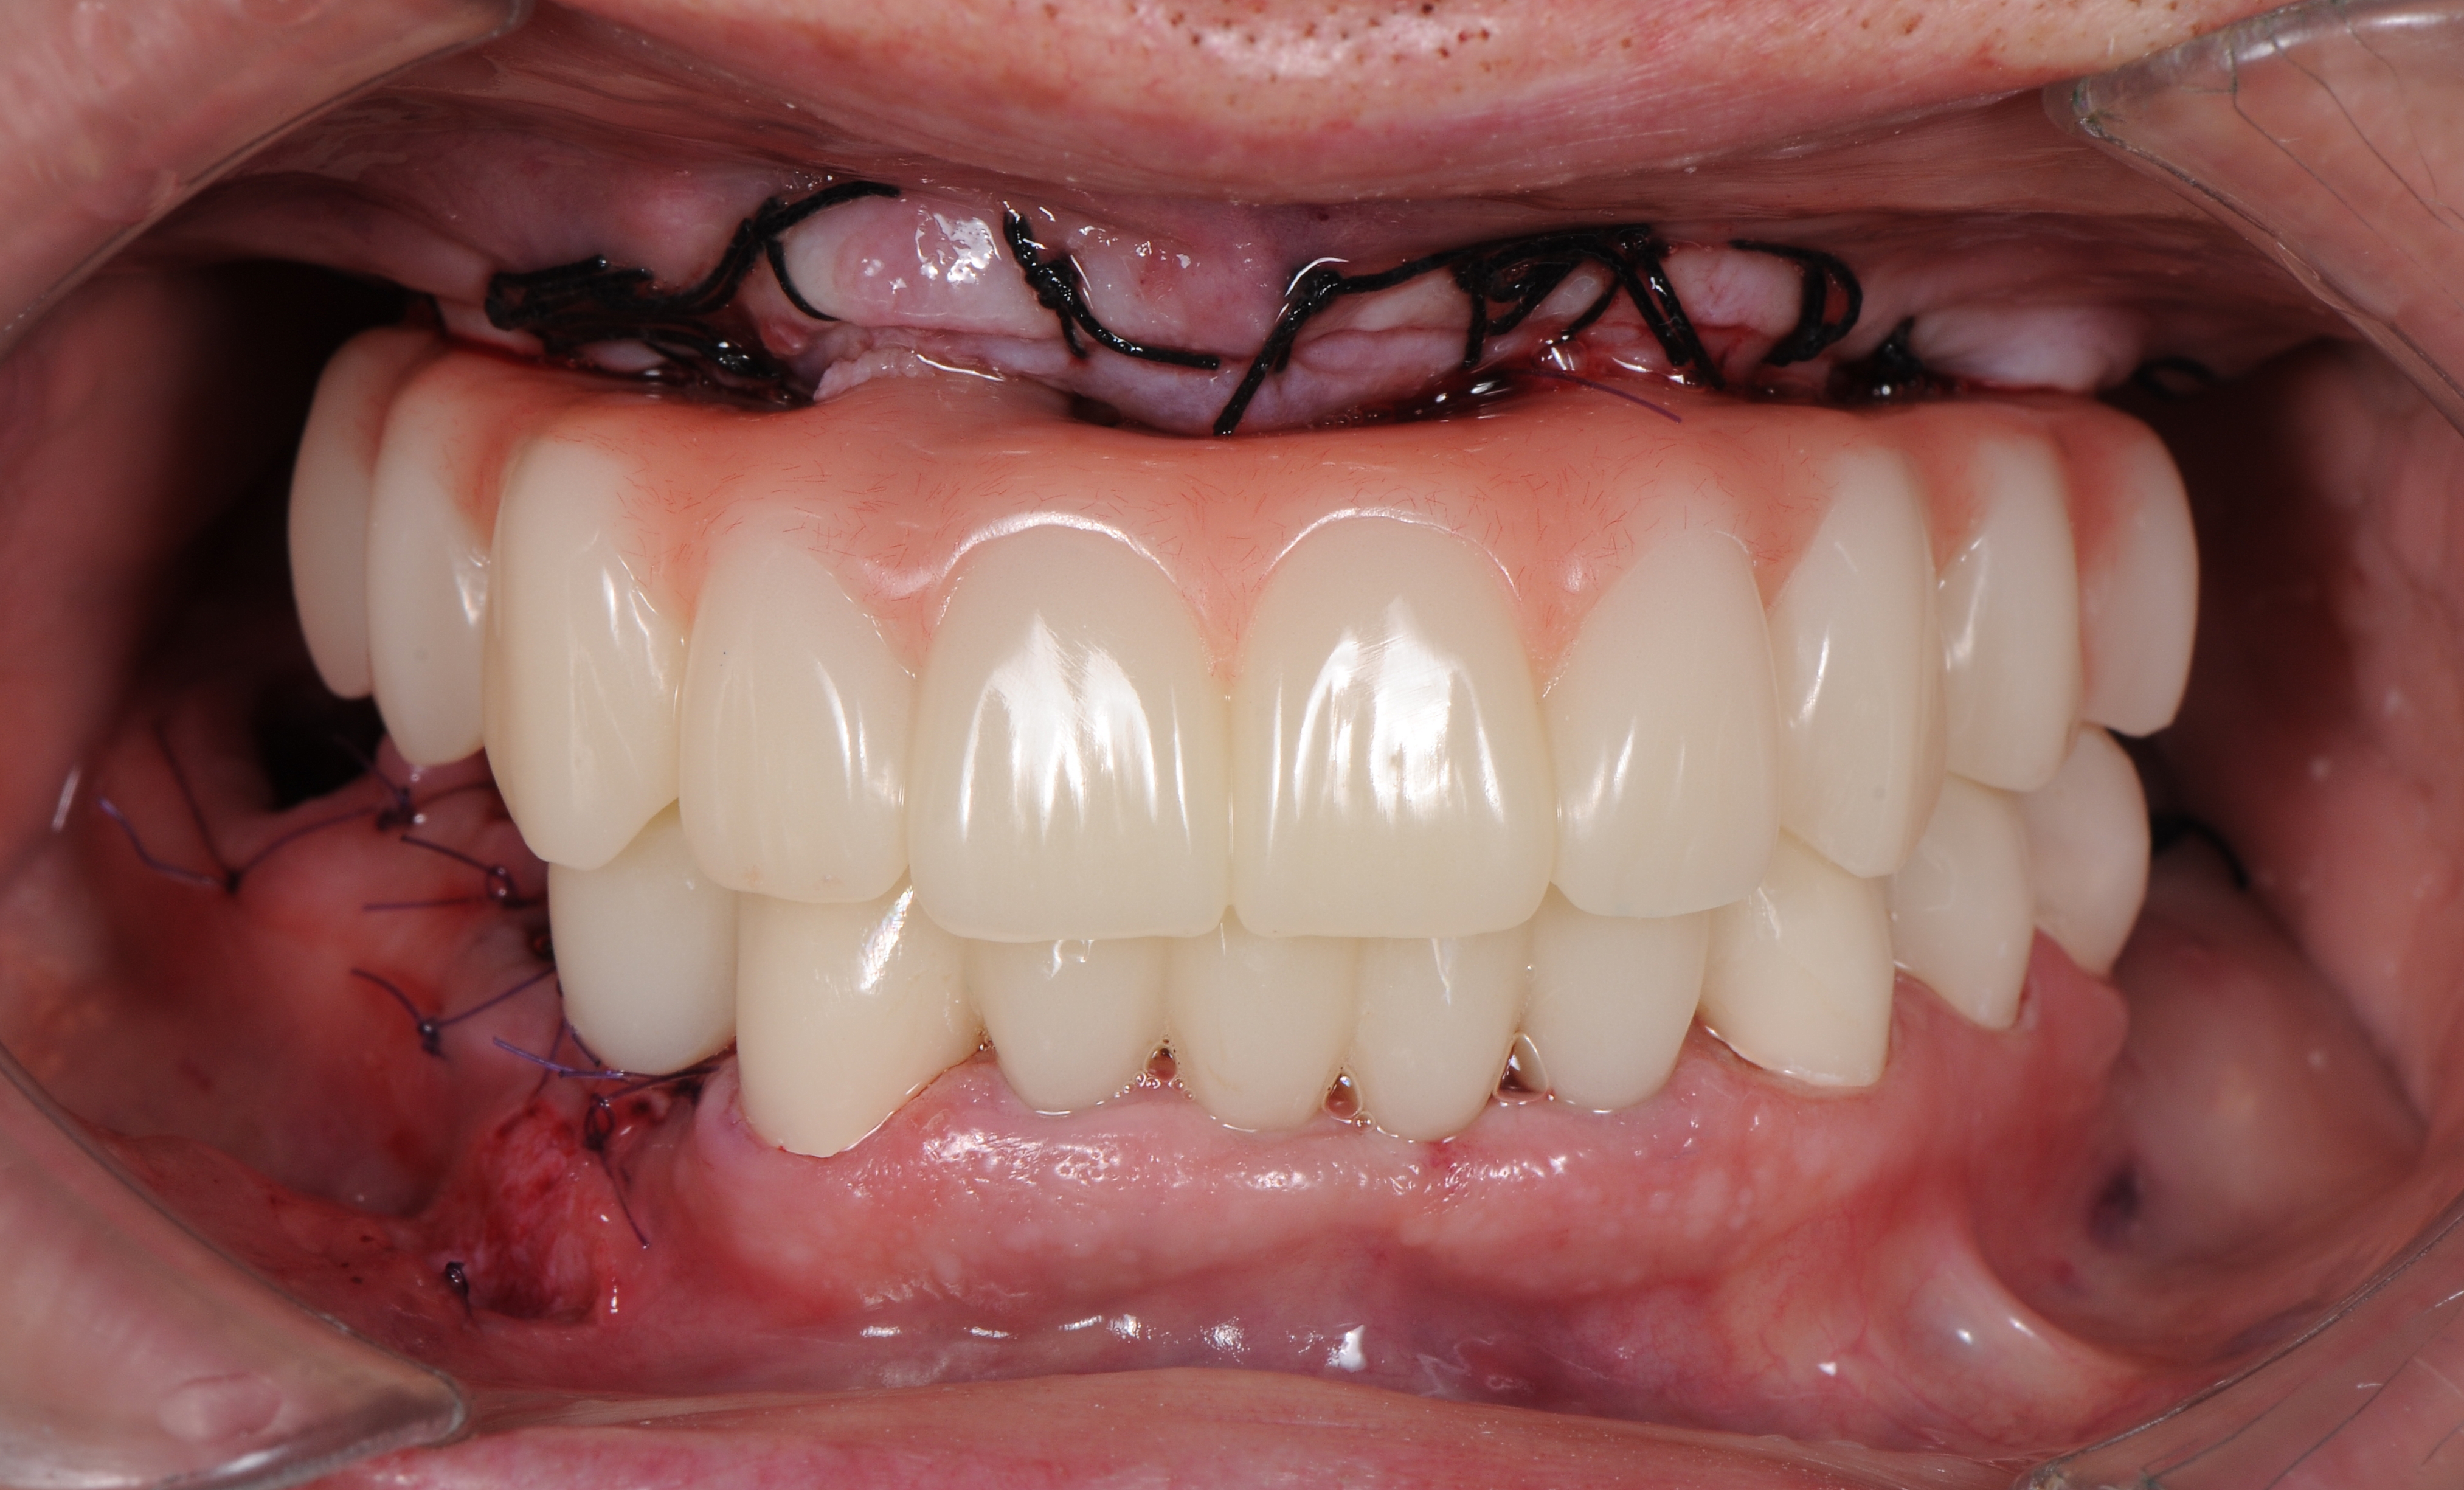

Фиксация временного протеза к абатментам в полости рта пациента с усилием 15 N/см2 окклюзионные контакты только в переднем участке (от клыка до клыка) (рис. 36,37).

Контрольная панорамная рентгенограмма после имплантации и установки временного протеза на верхней челюсти (рис. 38) По плану лечения также на нижней челюсти установили имплантаты в области 3.6, 4.4 и 4.6 зубов. Зубы 3.5, 3.4,3.3 – 4.3 были предварительно восстановлены мостовидными несъемными временными коронками из полиметилметакрилатного материала.

Через 10 дней после имплантации пациент приглашен для контрольного осмотра и снятие швов (рис. 39).